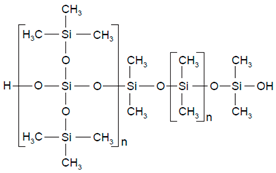

| Polymers | Structure | Fabrication Method | Commercial Products/Literatures | Comments | Reference |

|---|---|---|---|---|---|

| Polycarbonate (PC) |  | Ion-track etching | Estrogen | Excellent stability against oxidation and biodegradation and improves antifouling properties | [151] |

| Polyethylene (PE) |  | Ion-track etching | Catapress (Clonidine), Boehringer IngelheimClimara (Estradiol), Berlex | Physico-chemical stability andordered pore formation with superior membrane performance | [152] |

| Polyethylene terephthalate (PET) |  | Lithography | Ketoprofen | Biostable, antifouling, has better performance of membranes, in useful in preparing surgical meshes and ligaments | [153] |

| Polystyrene (PS) |  | Lithography | d-limonene, ibuprofen | Chemical resistance, easy processing, lower cost, exhibits enhancements in strength, stiffness, toughness, and ductility | [154] |

| PC, PE | - | Ion-track etching | Estraderm (Nitroglycerin), Rotta Research | Cost-effective and biocompatibility is fairly good | [155] |

| PC, PE, PET, PS | - | Phase separation | Deponit (Nitroglycerin), Pharma SchwarzHabitrol (Nicotine), Novartis | Cost-effective and biocompatibility is fairly good | [154,156] |

| Polyurethane (PU) |  | Sol-gel/solvent casting | Vivelle (Estradiol), Novartis | Good elasticity, biodegradable, suitable for hydrophilic drugs, biocompatibility is fairly good | [154] |

| Polysiloxane (silicone) |  | Sol-gel/solvent casting | Prostep (Nicotine), Lederle, Transderm Nitro (Nitroglycerin), AlzaSyncro-Mate-C (Norgestomet) | Better insulation, excellent biocompatibility, and fabricated easily for hydrophilic drugs | [157] |

| Polyisobutylene (PIB) |  | Solvent casting | Aminopyrene, Mitsubishi Petrochem Co., Japan | Good adhesive drug impermeable layer and high degree of tack or self-adhesion | [158] |

| Polymethyl methacrylate (PMMA), poly (2-hydroxy ethyl methacrylate) |  | Layer by layer deposition | Androderm (Testosterone), SmithKline Beecham | Physical strength and transparency | [159] |

| Polyvinyl alcohol (PVA), Poly (ethylene-co-vinyl acetate) |  | Solvent casting | Nitro-Dur I (Nitroglycerin), Key PharmaTestoderm TTS (Testosterone), Alza | Rate-controlling membranes, high membrane permeability, hydrophilicity and strength, suitable for lipophilic drugs | [160] |

| Polyacrylic acid, polyacrylate, polyacrylamide |  | Layer by layer deposition | Epinitril (Nitroglycerin), Rotta ResearchMonsanto (Fentanyl), Dow Corning | Good adhesivity and spreadability and contains a drug impermeable layer | [160] |

| Polylactides (PLA), polylactic-co-glycolic acid (PLGA), polyglycolides (PGA) |  , ,  | Sol-gel/solvent casting | Propranalol, Exxon Chemical Co. | Good biocompatibility; lactic and glycolic acids are the degradation products and they are easily eliminated from the body | [161,162] |

| Polyvinyl pyrrolidone (PVP), poly (N-vinyl pyrrolidone) |  | Sol-gel/solvent casting | Cytarabine, ara-ADA, Polyscience | Superior biocompatibility, has suspension capabilities, antinucleating agent, and enhances release rate | [163] |

| Polyethylene glycol (PEG) | Sol-gel/solvent casting | Miconozale, Rohm, Germany | Chemically inert and free of leachable impurities | [164] | |

| Oxide plus polymer | - | Sol-gel/solvent casting | Superior biocompatibility and has narrow pore size | ||

| Polymer coating on support membrane | - | Layer by layer deposition | [165] |